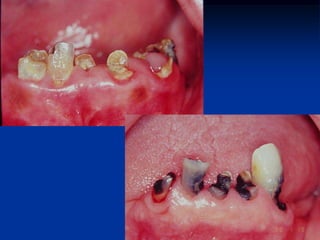

EXEMPLOS

Retirado de: Newmann, Takei e Carranza, 2004